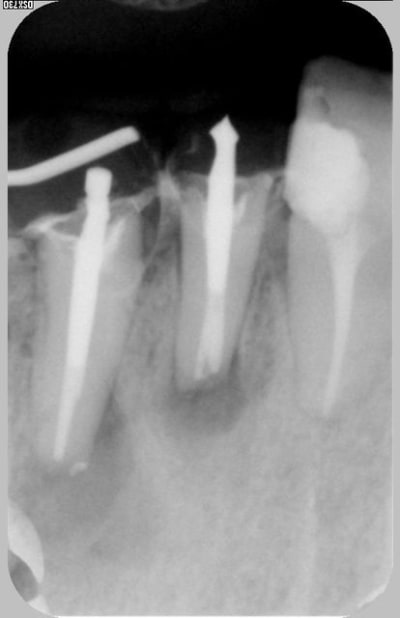

Après resec ejzcrl - Eugenol

je viens de voir votre post et vous mets une réponse en ligne avec quelques radios preop, postop, à 4 ans après et je vous dirai ce que j'ai mis pour obtenir ce résultat satisfaisant il me semble, par ailleurs vous me direz si en toute impartialité vous auriez opté pour la même option de tt ou si vous n'auriez pas fait l'exo et implanto.

à vous lire....